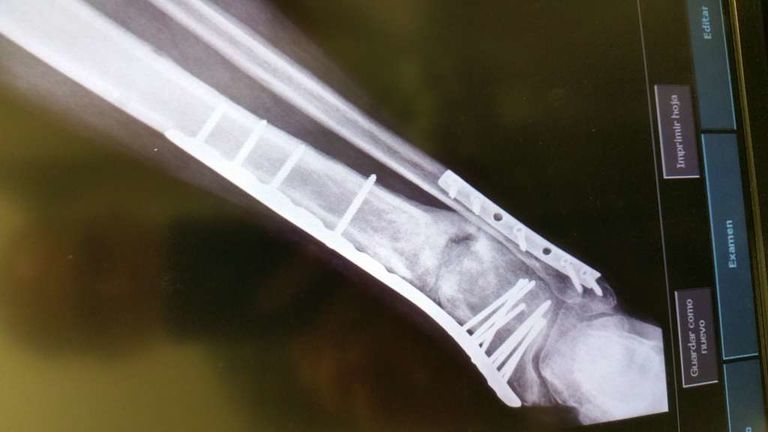

Mito Publicado 19 de Noviembre del 2014 Compartir Publicado 19 de Noviembre del 2014 Yo tuve un accidente de moto y me rompí la tibia y el peroné. Me tubieron que poner un clavo como el has puesto en las fotos y aún lo llevo, esto fue en el 2002 y ha dia de hoy no me molesta ni me lo voy a quitar. La rehavilitación fue muy muy lenta uffff y eterna. Estuve 3 meses sin poder poner el pie en el suelo, con muletas, la pierna se me quedó sin fuerza ninguna. En rehabilitación no notaba mejoría... creo recordar que pasó un año para que yo estuviera caminando normal. Me apunté a un gimnasio y ahí fue cuando recuperé toda la fuerza. Mucha paciencia y echarle muchas ganas de recuperación y siento mucho lo que te ha pasado, por que es superdoloroso y muy pesado -sombrero Enlace al comentario Compartir en otros sitios web More sharing options...

SuperGabaDink Publicado 19 de Noviembre del 2014 Compartir Publicado 19 de Noviembre del 2014 Mucho animo y paciencia compi! Me sumo a Mito ya que me paso algo parecido aunque tarde un poco mas...Una buena rehabilitación sumada a la que le eches tu aparte es la clave. A eso sumale una buena dosis de animo y positivismo pensando que te pondras bien aunque el proceso sea lento, y ya sera historia pasada. Yo me rompi tambien tibia y perone al caerme el scooter encima de mi pierna. La tibia en 3 cachos,desplazada,astillada etc...casi pierdo la pata. Llevaba mas hierros que Robocop y un sin fin de operaciones con injertos variados..jejeje; tarde 2 años en recuperarme,3 en olvidarme del tema y no cojear y 4 en poder volver a poner mi culo en una moto... No te desanimes,ya veras como en nada podras darle gas de nuevo. Enlace al comentario Compartir en otros sitios web More sharing options...

Andres1108 Publicado 19 de Noviembre del 2014 Compartir Publicado 19 de Noviembre del 2014 Solo con ver las radiografias me duele todo... Animo! Piensa que luego serás un motero bionico... mejorado artificialmente jajaja Un saludo Enlace al comentario Compartir en otros sitios web More sharing options...

jerolo Publicado 31 de Enero del 2016 Autor Compartir Publicado 31 de Enero del 2016 El lunes 1 placa y a ver como va la cosa,subiré foto PD. Cómo me duele la puta pierna :-) Enlace al comentario Compartir en otros sitios web More sharing options...